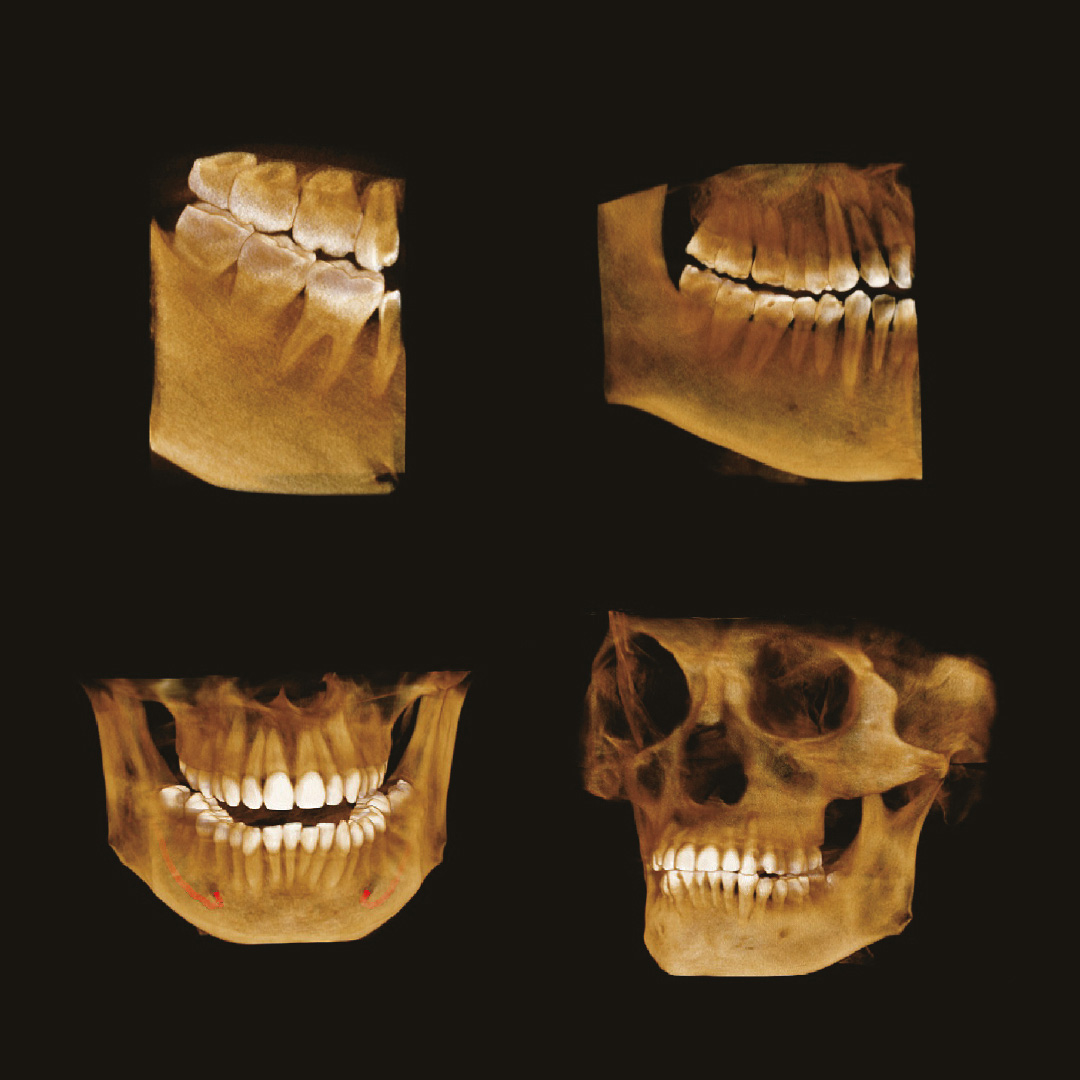

Пример 3D исследования дентального компьютерного 3D томографа Volux 55 Genoray.jpg

Высокотехнологичный детектор с самым высоким разрешением в классе – 70 мкм. Позволяет различить даже самые мелкие анатомические образования и облегчит постановку диагноза в сложных случаях. А вместе с применением алгоритма SMARF инородные тела из металла не испортят качество снимков.